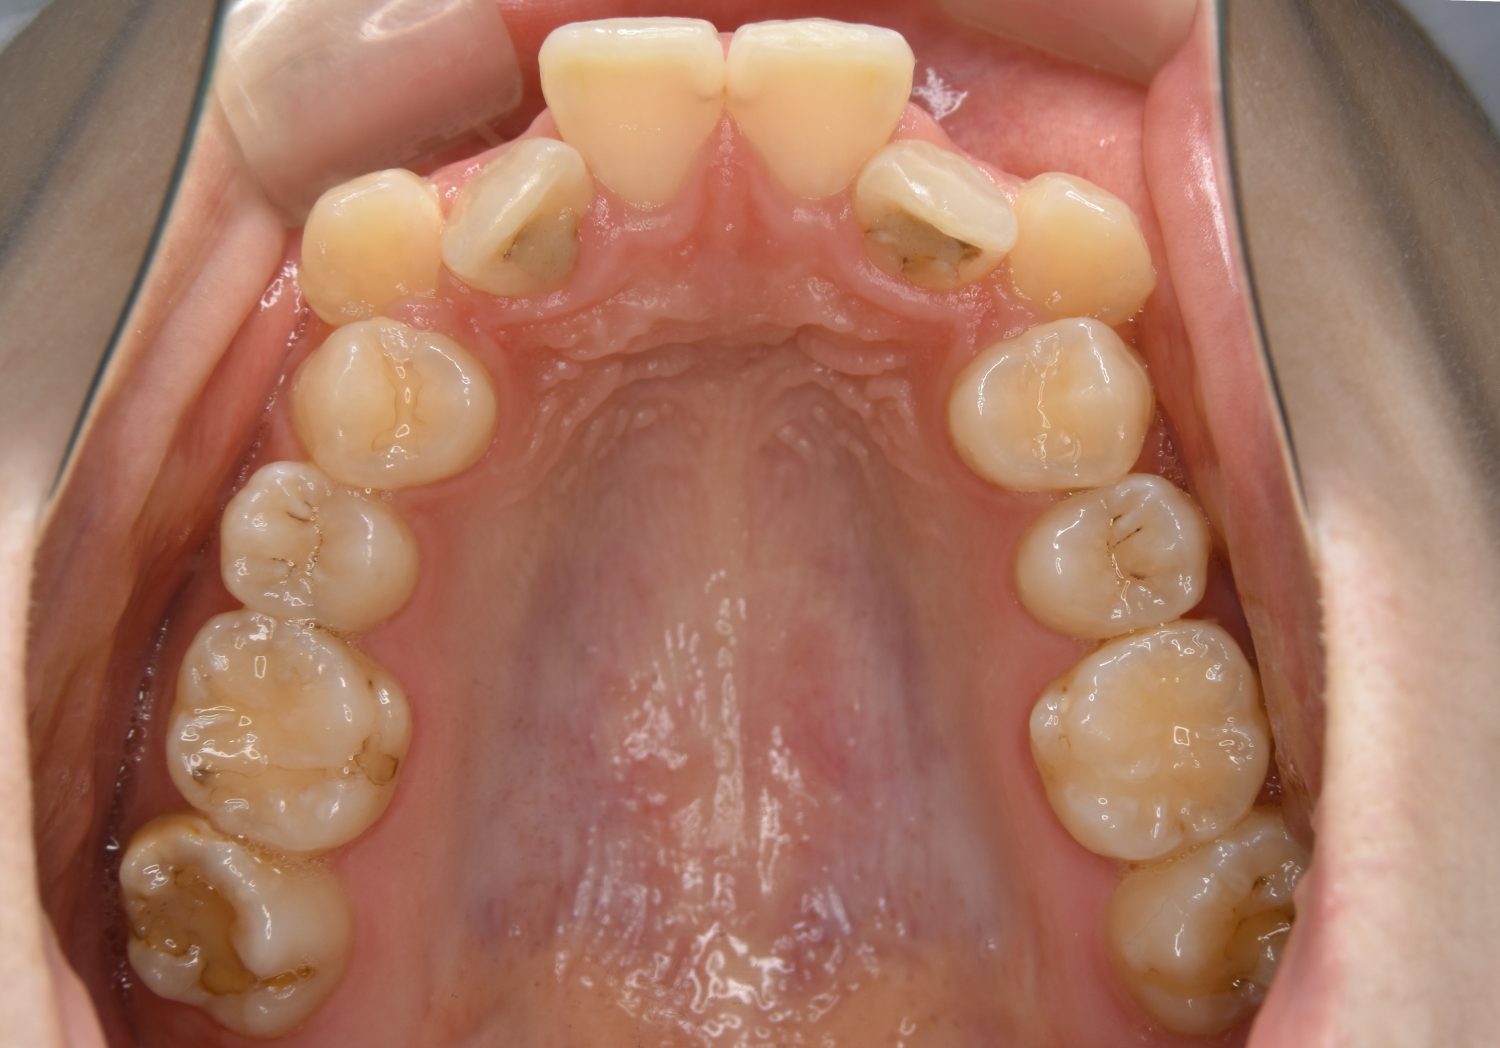

叢生の症例紹介②

Before

After

主訴

歯の凸凹を治したい。

治療内容

アライナー(インビザライン)にて非抜歯で治療を行いました。

治療費

1,150,000 円(税込)

治療期間

26ヶ月

通院回数

14回

想定されたリスク

※歯根吸収、歯肉退縮、歯髄壊死、顎関節症状

※アライナー(インビザライン)は日本の薬機法未承認の矯正装置であり、医薬品副作用被害救済制度の対象外となる場合があります。

丸山和宏先生

ピーススマイル矯正歯科

上下前歯部に叢生(凸凹)が認められる状態でした。歯列の遠心移動を行うことで機能面および審美面が改善されました。